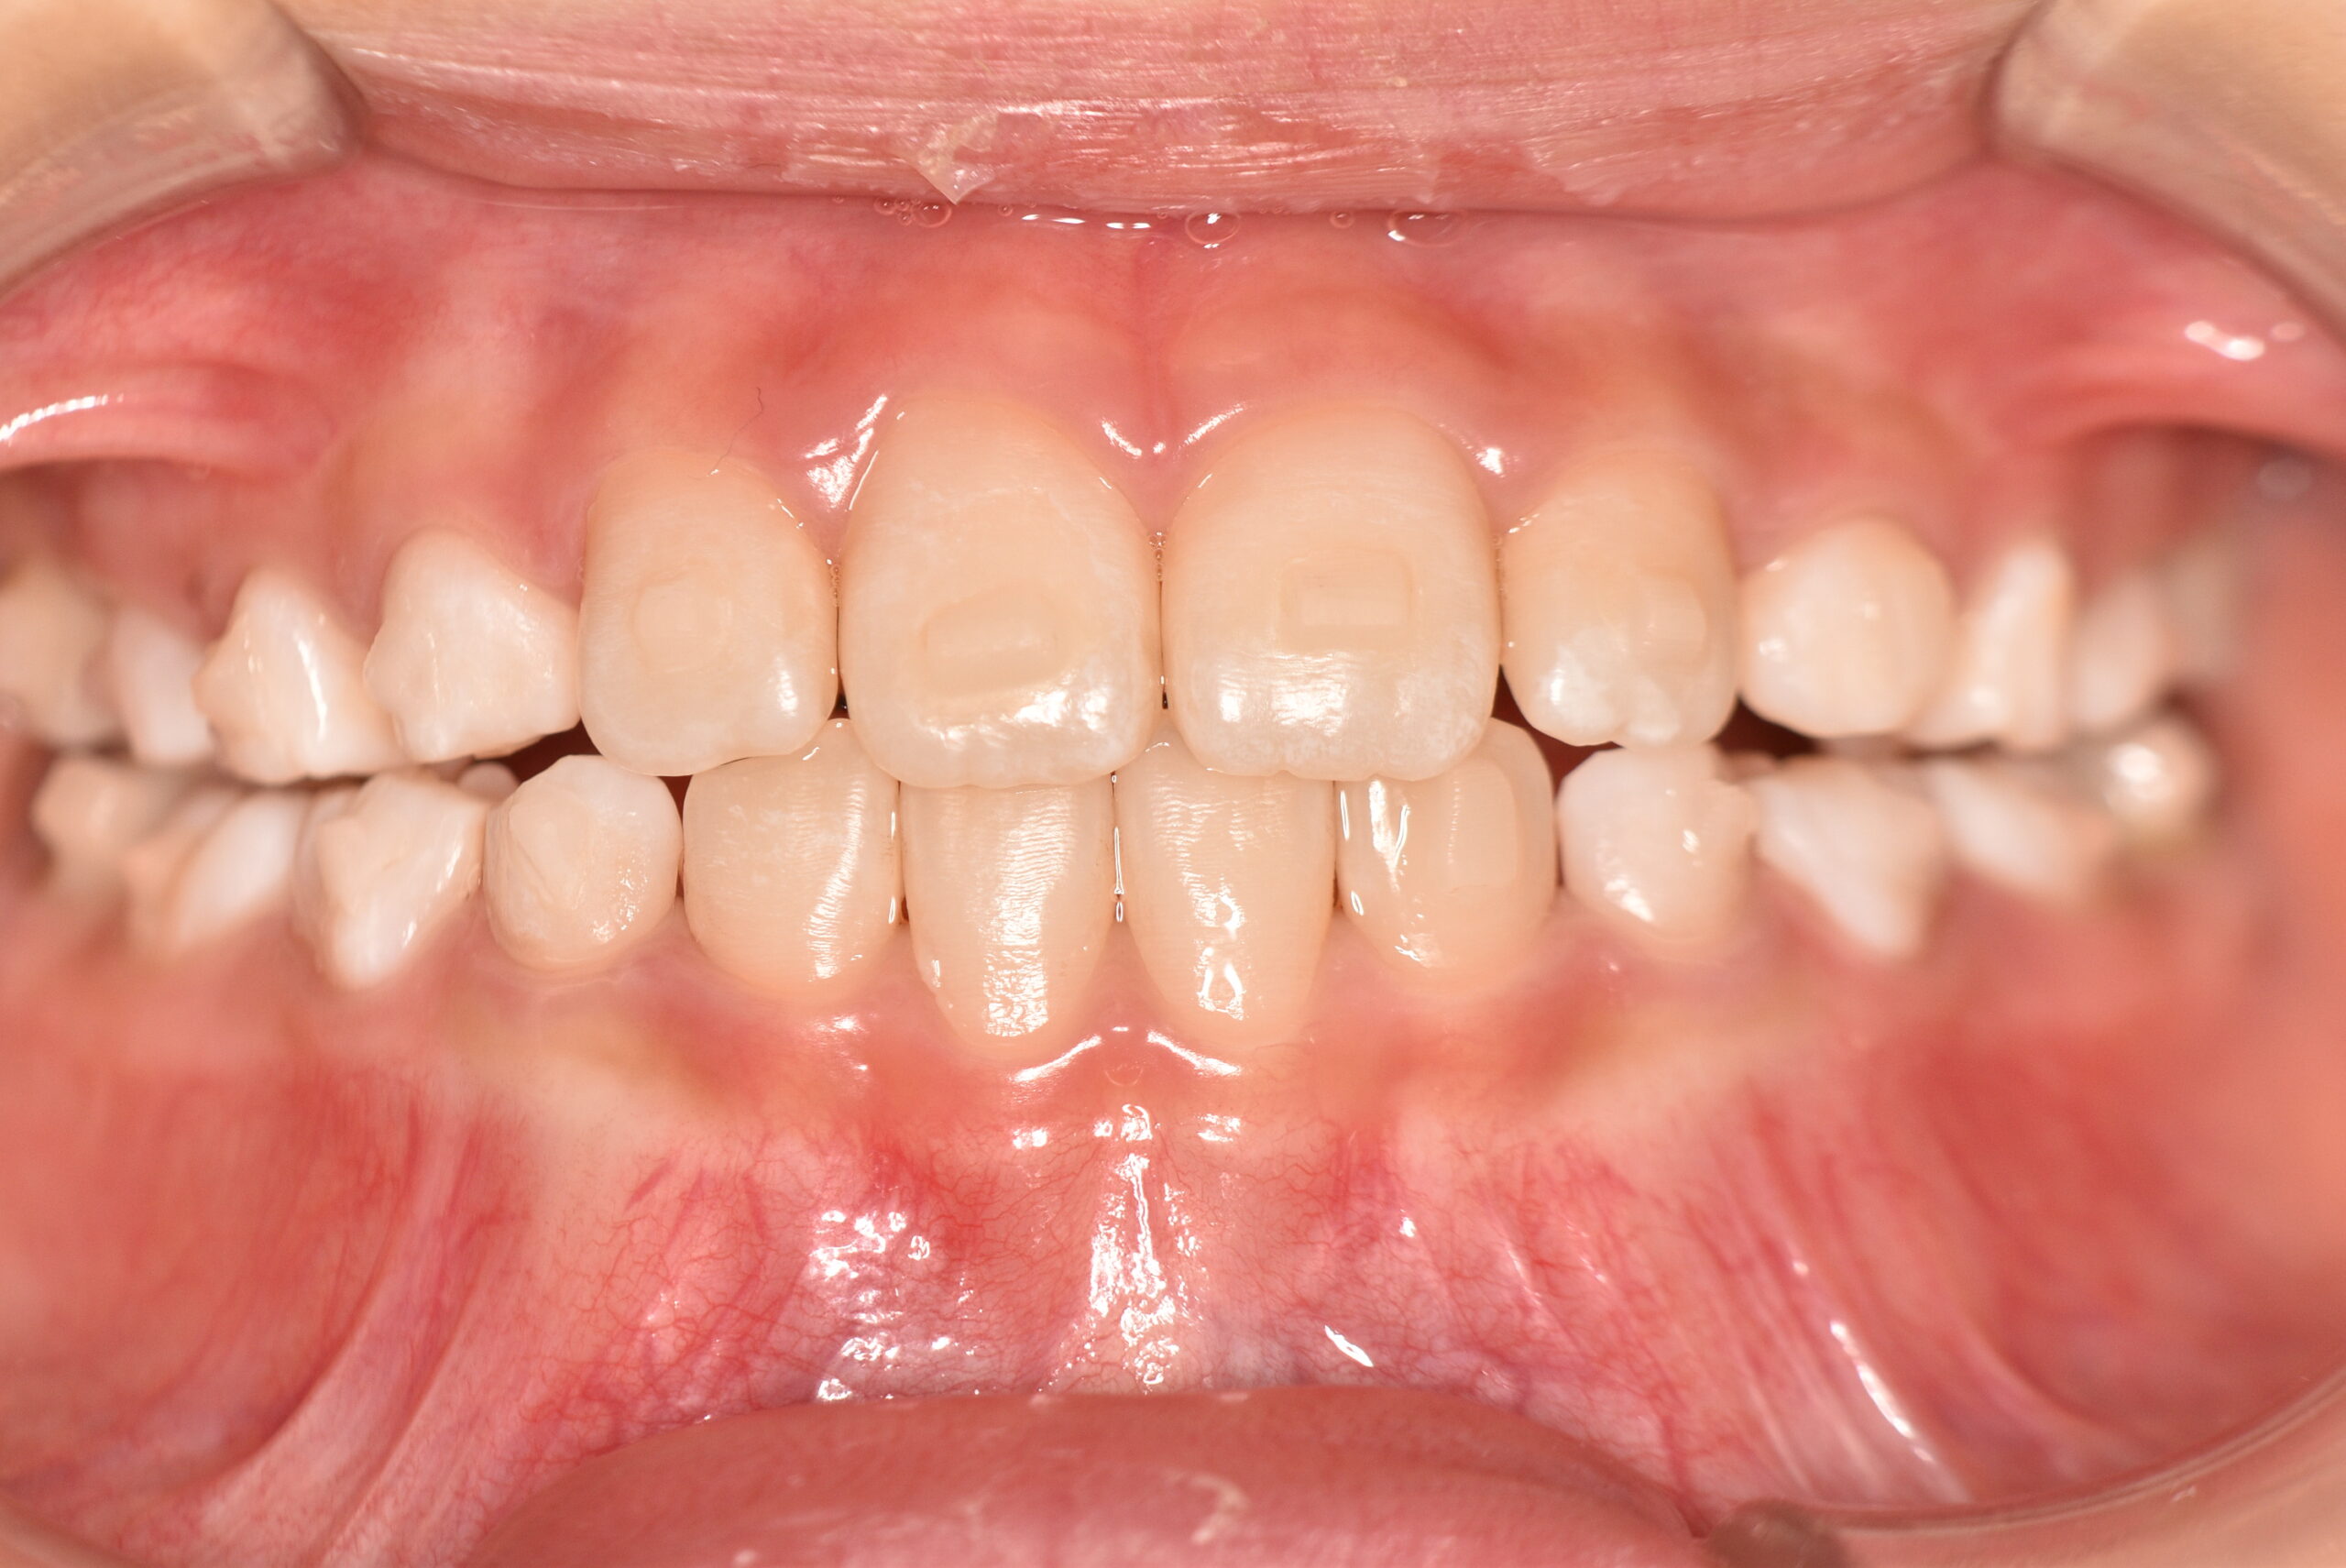

動的治療終了時

症例 症例 症例 症例

治療としてはマウスピース矯正(インビザラインファースト)で配列を行い、上下顎の側方拡大と萌出スペースを確保しました。

治療期間は、7ヶ月でした。

今後、側方歯生え変わりまで経過観察を行います。